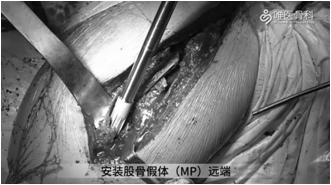

①充分冲洗后给予股骨髓腔扩髓、预绑钢丝,然后安装股骨假体(MP)远端,安装MP假体近端试模。